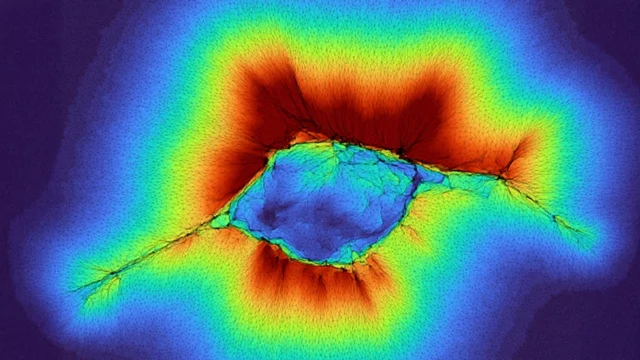

Essa capacidade de detecção depende em parte de como as células puxam e remodelam o colágeno fibroso ao seu redor. Ao deformar essas fibras, as células estendem suas antenas para a matriz extracelular (MEC) e podem “sentir” o conteúdo da camada subjacente. A próxima camada pode ser algo duro, como um tumor, um tecido mais mole ou até mesmo um osso próximo. Ao testar a rigidez da MEC, uma única célula anormal pode determinar a direção na qual ela deve se mover.

Novas pesquisas mostram que populações de células epiteliais que formam a superfície de muitos tecidos poderiam permitir um maior alcance de detecção. Quando essas células trabalham juntas, elas geram força suficiente para sondar o colágeno fibrilar e detectar camadas tão distantes quanto 100 mícrons.

Modelos computacionais mostram que o processo se desenvolve em dois estágios, à medida que as células se aglomeram e começam a migrar. Durante esses estágios, as informações que as células reúnem sobre o ambiente afetam a forma como elas se movem e se espalham.